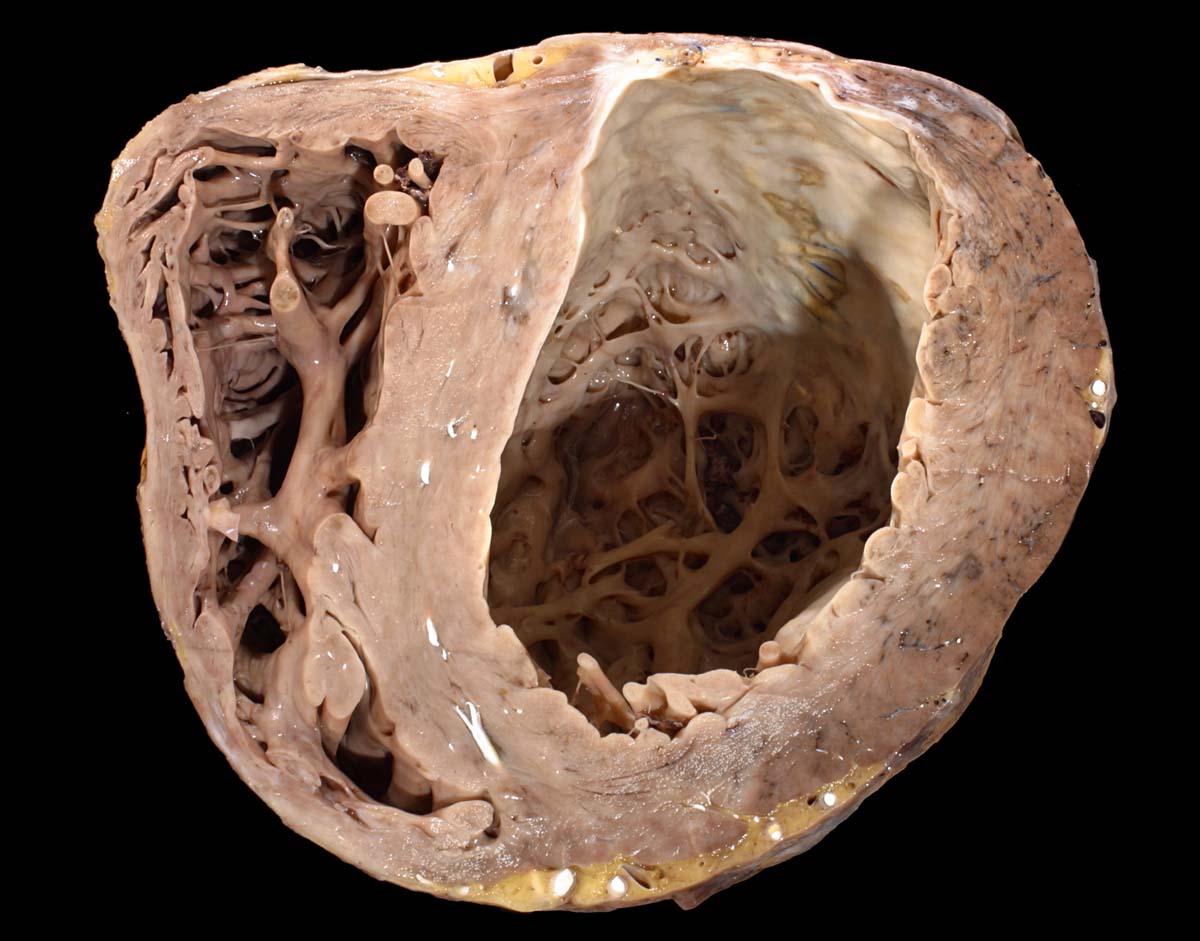

Eine restitutio ad integrum nach abgelaufener Myokardnekrose ist nicht möglich. Wird das Ischämieereignis überlebt, kommt es zu einer reparativen Regeneration mit Ersatz der Muskulatur durch kollagenreiches Narbengewebe. Dieser Vorgang setzt etwa ab dem 9. Tag nach Infarkt ein und dauert bis zur vollständigen narbigen Ausheilung bei transmuralem Infarkt etwa 50 Tage. Makroskopisch imponiert die Narbe als fasriges weisses derbes Areal. Von einem Infarkt spricht man, wenn die Nekroseareale einen Durchmesser von mindestens 3cm Durchmesser haben. Ab dieser Grösse kann klinisch das Bild eines Myokardinfarktes ausgelöst werden. Kleinere, makroskopisch sichtbare Narben werden als grobfleckige Myokardfibrose (> 873) (> 234) bezeichnet.

Im Bereich grösserer Narben ist das Myokard verdünnt. Bei 8% der transmuralen Infarkte entsteht im Bereich der Narbe ein Herzwandaneurysma (> 2088) mit oder ohne wandständige Thrombose (> 348). In 5-15% führen die Thromben zu systemischen Embolien. Von der Randzone der Aneurysmen gehen oft hartnäckige ventrikuläre Rhythmusstörungen aus. Grosse Narben führen zu einer Verminderung der Pumpleistung mit Herzinsuffizienz.

Morphologische Merkmale:

• Herdförmiger Ersatz der Muskulatur durch zellarme rote Kollagenfaserbündel.

• Hypertrophiezeichen der Herzmuskulatur im Randbereich der Narbenareale (verdickte Herzmuskelzellen mit vergrösserten hyperchromatischen Kernen).

• Im untersten Biopsiefragment sind die Narbenareale bandförmig subendokardial verteilt. Zwischen Narbengewebe und Endokard findet sich eine schmale Schicht erhaltener Muskelzellen (Ernährung dieser Zellen per Diffusion direkt aus dem Herzblut).